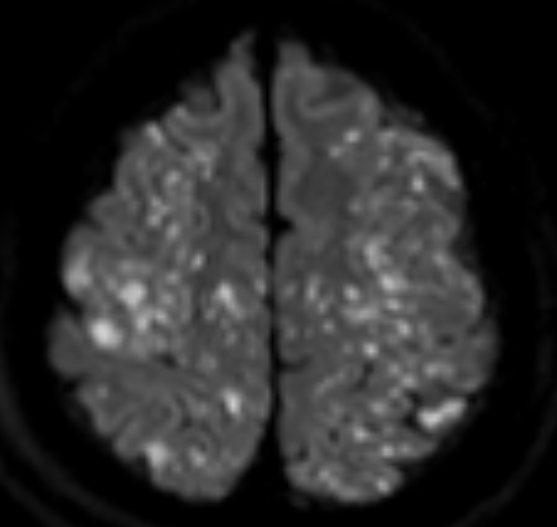

1) Starfield pattern (별자리 패턴)

· DWI에서 고강도 신호가 다발성으 나타남.

· 미세색전이 뇌의 회백질(gray matter) 과 백질(white matter) 에 광범위하게 분포.

· 해당 패턴은 CFE의 대표적인 소견이며, 매우 특징적인 영상 소견!